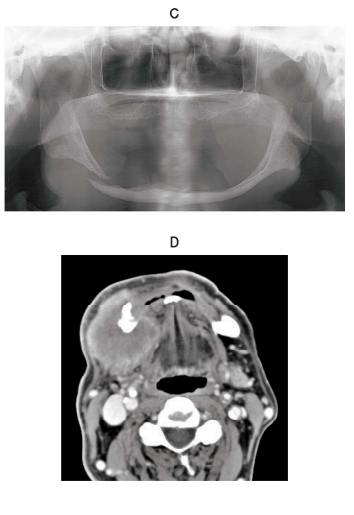

118回 A-37

80 歳の男性。右側下顎体部の腫脹と疼痛を主訴として来院した。 5 日前に硬固物を咀嚼した後から腫脹と右側オトガイ神経麻痺を認めたという。頸部に腫大したリンパ節は触れない。初診時の顔貌写真(別冊No. 10A)、口腔内写真(別冊No. 10B)、エックス線画像(別冊No. 10C)、造影 CT(別冊No. 10D)、MRI 脂肪抑制 T2強調像(別冊No. 10E)及び生検時の H-E 染色病理組織像(別冊No. 10F)を別に示す。

診断名はどれか。 1 つ選べ。

解答:c

解説:

画像C:下顎骨右側骨折

画像DE:T2強調画像なので水分が白くなる。境界不明瞭

画像F:癌真珠がみられる

a 骨肉腫:X線画像にサンレイアピアランスがみられる

b 腺様囊胞癌:病理組織像で篩状構造が特徴

c 扁平上皮癌:○骨折は扁平上皮癌の浸潤による。

d 悪性リンパ腫:もっとリンパ球がみられる。

e 多発性骨髄腫:腫瘍性の形質細胞がみられる。